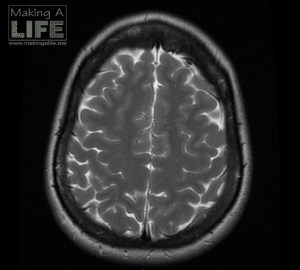

My Brain 1 Sharing is caring: Share on Facebook (Opens in new window) Facebook Share on Pinterest (Opens in new window) Pinterest Share on X (Opens in new window) X Share on Tumblr (Opens in new window) Tumblr Email a link to a friend (Opens in new window) Email More Print (Opens in new window) Print Share on LinkedIn (Opens in new window) LinkedIn Share on Reddit (Opens in new window) Reddit Like Loading...